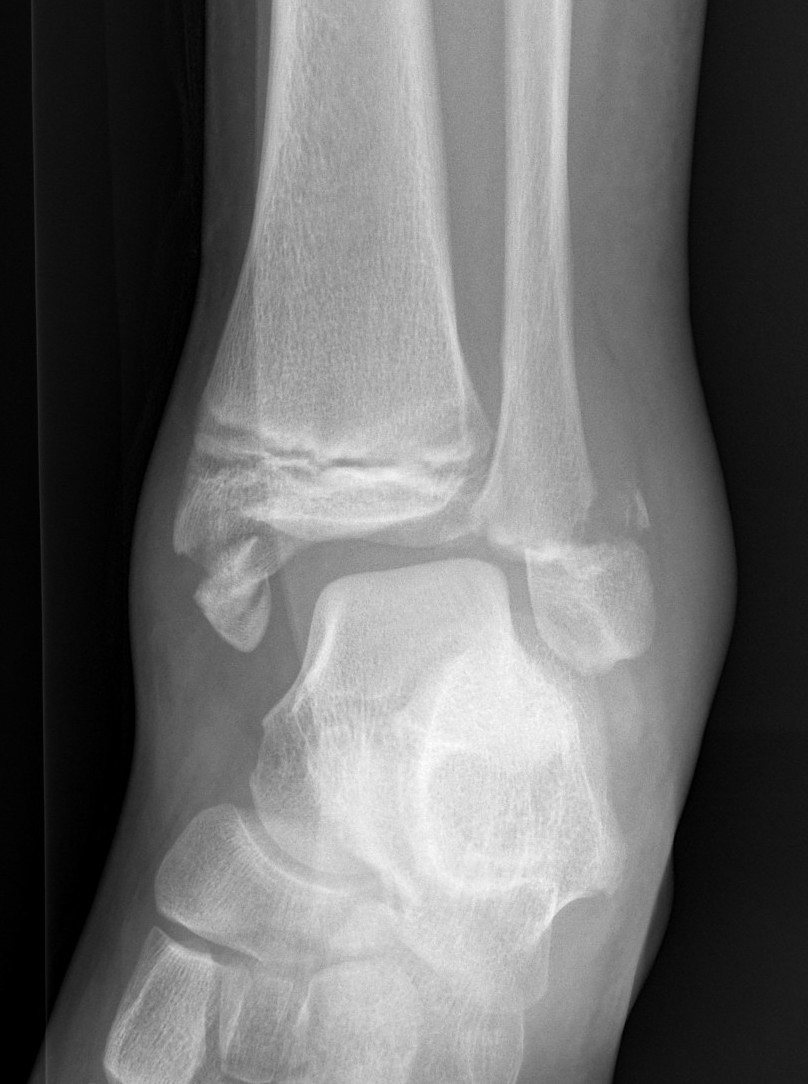

Triplanar Fracture

Definition

Fracture in coronal, sagittal and transverse planes

- crosses epiphysis

- passes through growth plate

- extends into metaphysis

Xray

AP xray: Salter-Harris type III / Tillaux

Lateral xray: Salter-Harris Type II